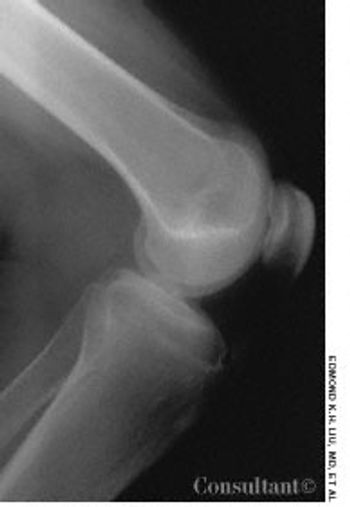

For the past 3 years, a 17-year-old boy had experienced intermittent pain in the right knee. The pain worsened when he went up and down stairs, ran, jumped, or knelt.